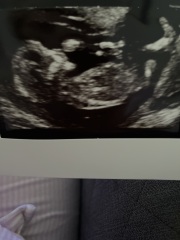

Tr1998 · 01/08/2024 20:17

13+4 any guesses